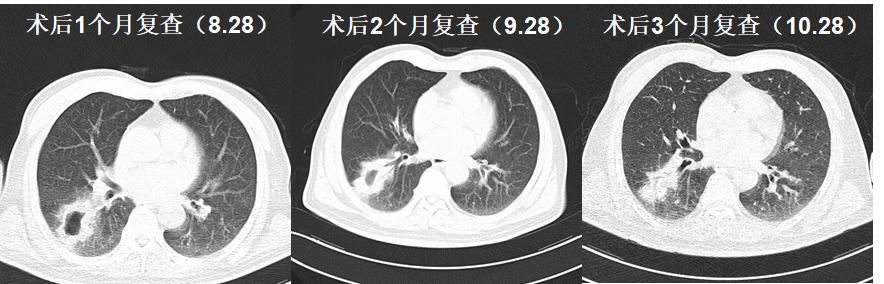

术后影像学检查